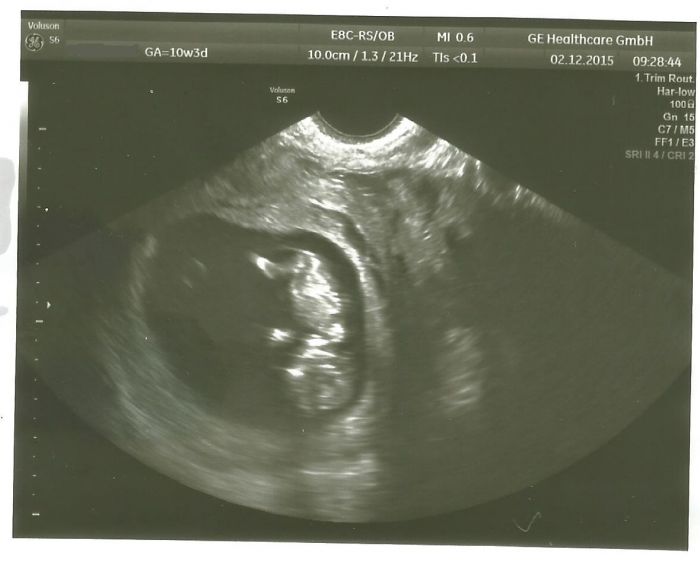

tak jsem dnes byla na odběru krve a předtím ještě na kontrole, tak jsme mrkli na mimouše a je v pořádku, tancuje tam na hlavě - fakt se točil na hlavě a máchal u toho ručičkama i nožičkama, doktorka se smála, že sebou teda mrská vydatně. Má asi 3,6 cm CRL, myslím, odpovídá 10+4 a jsem 10+3. Už u první kontroly odpovídal o den víc, tak udržuje tempo růstu.

No a ještě teda fotka toho mého prďolínka: